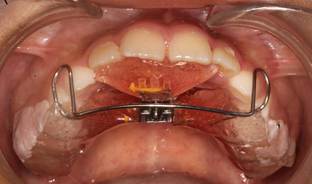

Indicaciones del aparato

Fig. 13 Vista frontal del aparato de Eschler Fig. 14 Vista de 45° con el aparato de Eschler

El arco de Eschler con tornillo triple debe usarse entre 18 y 20 horas diarias, incluyendo durante el sueño, y retirarse solo para comer, cepillarse y hacer deporte. Debe limpiarse a diario con cepillo suave y jabón neutro o pasta dental, y guardarse en su caja rígida cuando no se use. No debe mojarse con agua caliente ni dejarse al sol.

Se le indica al paciente y su acudiente que las activaciones del tornillo se harán en consulta, siguiendo indicaciones precisas del ortodoncista. También que es fundamental asistir puntualmente a los controles periódicos y se requiere del compromiso de ambas partes para lograr el objetivo del tratamiento, ya que el mismo depende en gran parte del uso constante, la buena higiene y el cumplimiento de las indicaciones.